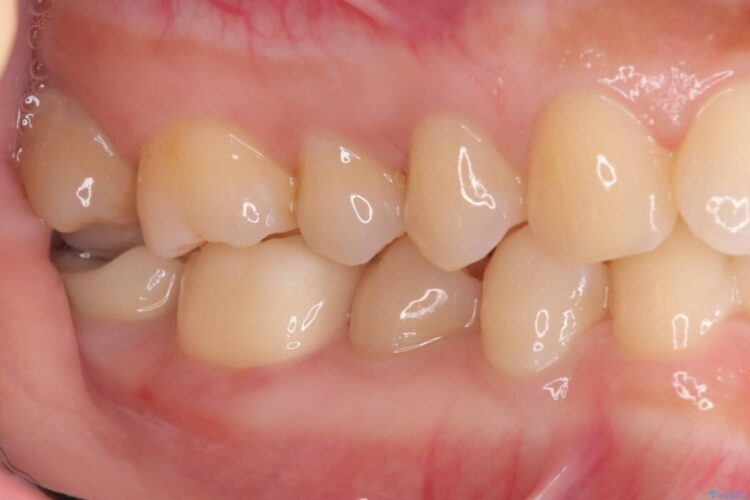

以前に詰めた白い詰め物の内部で、虫歯の再発が確認されました。